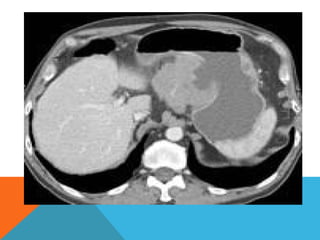

Computed tomography

Typically gastric lymphomas demonstrate marked

thickening of the stomach wall (2-4cm) with extensive

lateral extension of the tumour (i.e. along the wall of

the stomach) representing submucosal spread.

 Submucosal spread may

 Encompasses the majority of the stomach giving a

linitis plastica appearance.

 Can extend across the pylorus into the duodenum

and superiorly into the oesophagus.

 uncommon for lymphoma to result in

gastric outlet obstruction